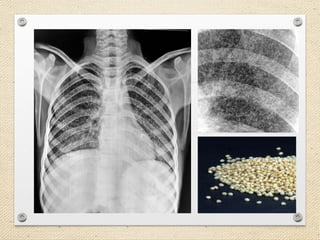

Chest X-Ray

• Typical appearance only in 50% of cases

• Bilateral pleural effusions indicate dissemination.

This may be a useful clue.

• Nodules characteristic of miliary TB may be better

visualized on lateral chest radiography (especially

in the retrocardiac space).

• Nodules are the size of millet seeds (1-5mm,

mean=2mm)

Chest X-Ray • Typicalappearance only in 50% of cases • Bilateral pleural effusions indicate dissemination. This may be a useful clue. • Nodules characteristic of miliary TB may be better visualized on lateral chest radiography (especially in the retrocardiac space). • Nodules are the size of millet seeds (1-5mm, mean=2mm)